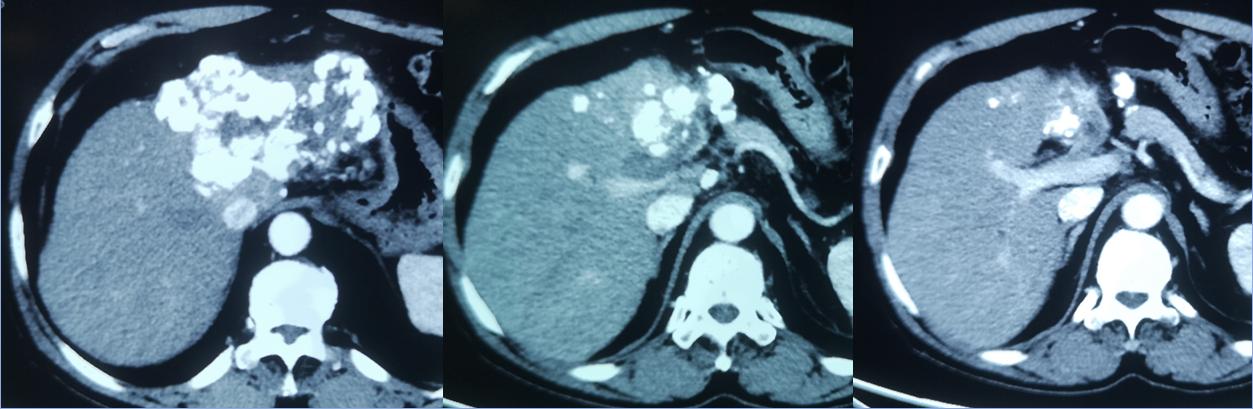

3个月后复查CT显示碘化油沉积效果好 AFP: 16.9ng/ml

最终,通过肝动脉栓塞化疗、消融、中医调理等,成功控制了肿瘤的生长,在随后的复查中,肿瘤逐渐减小,肖先生的生活质量明显改善。